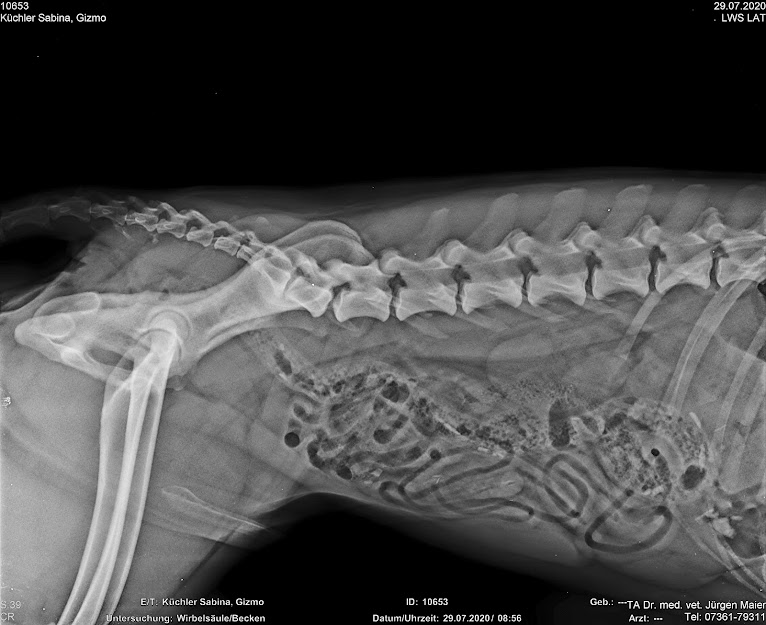

Hier nun noch die beiden Röngten von Gizmo wo der Übergangswirbel zu sehen sei, wo mich hier besonders interessiert, ob ihr den zum Einen auch seht und zum Anderen, welche Stufe von Übergangswirbel das wohl ist - 0 bis 3?

Beim Betrachten des Bildes wurde unser Tierarzt aber stutzig. Er zählte und zählt mehrmals und fand dann raus, dass Gizmo einen Übergangswirbel hatte.

Da das eine Erkrankung ist die bei Schäferhunden vorkommt hoffe ich, dass ich hier Tipps bekommen werde.

DAS Röntgen ist schon von 2020. Denn als wir Gizmo bekamen, ließ ich ihn erst mal komplett durch checken, denn unser vorherigen Bingo hatte HD, welche erst nach 3 Tierärzten und 6 Kliniken (!) entdeckt werden wollte.